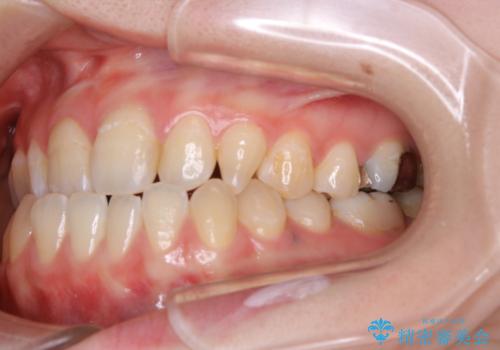

- 受け口で、前歯の嚙み合わせが気になるとの事でご相談にいらした方です。先天的に右上犬歯がなく、左上犬歯も小さい状態でした。矯正治療にて周囲の歯を動かして歯のスペースを確保した上で、被せものにて歯を作っていきました。

歯科技工士さんの熟練した技術により、周囲の歯としっかりなじむ天然歯のような被せ物をお作りすることが出来ました。

矯正治療と補綴治療をうまく組み合わせることで、美しい口元に仕上げることが出来ました。矯正治療、補綴治療をまとめて行える総合歯科治療を体現した治療といえます。